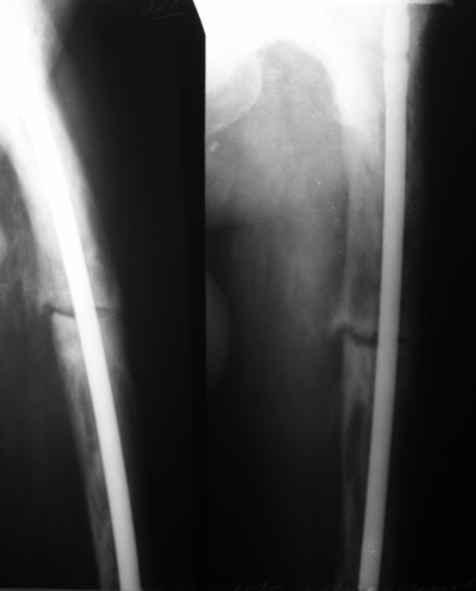

бывали ли у кого-нибудь такие случаи Уважаемые коллеги, вчера прооперировал женщину 60 лет с болезнью Педжета, переломом верхней трети бедра. Выявлена в августе этого года, сломала три дня назад от небольшого усилия. Из сопутствующих болезней лейкоз, сахарный диабет. Бывали ли кого-нибудь такие случаи, чем это все заканчивалось?

Еще один пример. Пациентка с юга России, прислала рентгенограммы через год. На сегодня прошло 2 г. 8 мес. после операции. Несмотря на не очень убедительный процесс сращения, пациентка ходит. Учитывая остеопороз при Педжете, решили, что динамизировать вообще не нужно.

При переломах на фоне болезни Педжета металлоконструкция часто служит эндопротезом, несущим нагрузку. Динамизация индивидуальна,- по рентген-динамике. Основной упор- на медикаментозную терапию- см. канд. дисс. Колондаева А.Ф.